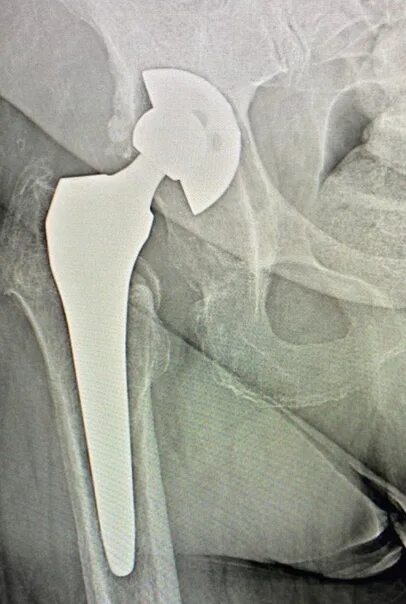

Состояние после эндопротезирование тазобедренного сустава мкб